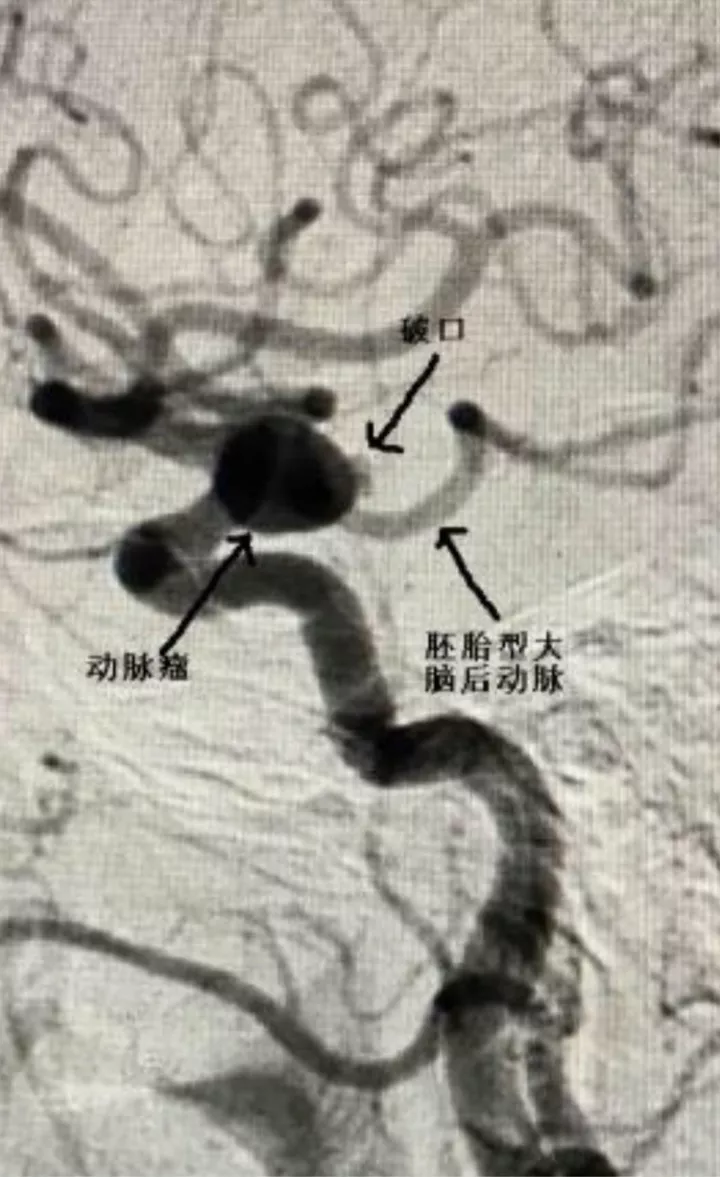

女,73岁,蛛网膜下腔出血量还挺多的,H-H 分级4级

造影显示左侧后交通动脉瘤

椎动脉造影没发现大脑后动脉,双侧的大脑后动脉都是由颈内动脉-后交通动脉发出,双侧胚胎型大脑后动脉